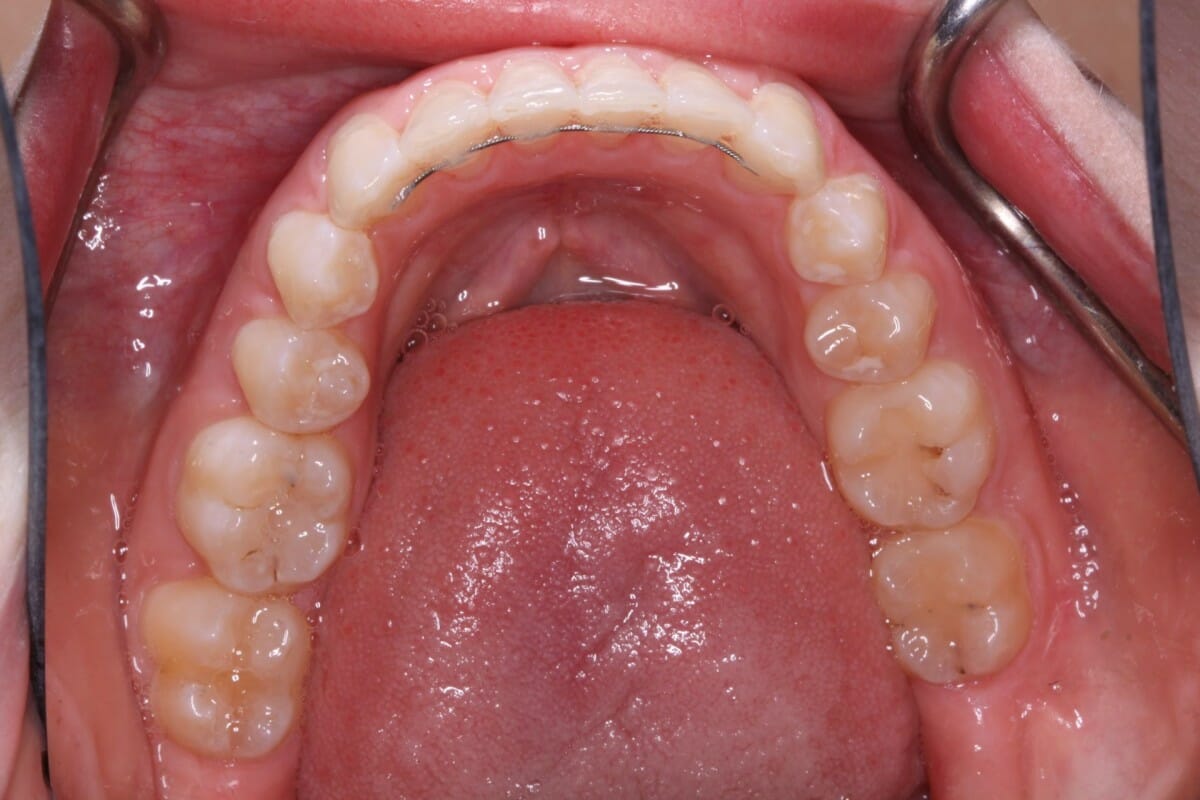

Crown & Veneer

After